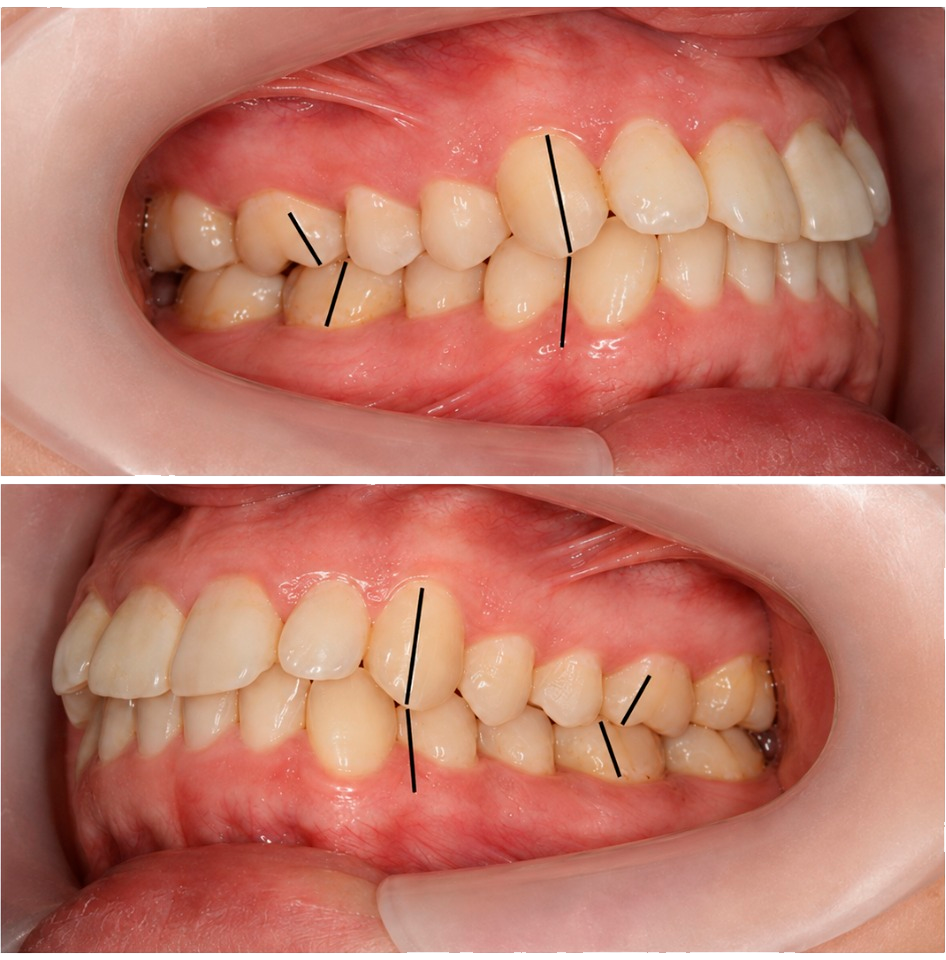

Один из главных критериев выбора – это профессионализм стоматолога ортодонта.

Дело в том, что самое важное в установке брекетов – это правильно скорректировать прикус. Начинающие доктора не знают, как правильно произвести расчеты, чтобы уже через пол года прикус был исправлен!

Поэтому, если Вы попадете к неопытному ортодонту, процесс исправления прикуса может занять до 3-х лет и при этом никакой гарантии результата.

Восстанавливаем прикус в кратчайшие сроки

- Прием ведут опытные ортодонты. Опыт врача напрямую влияет на сроки исправления прикуса.

- Перед началом лечения осуществляем максимально детальную диагностику на основании ТРГ снимков.

- С помощью специального программного обеспечения с математической точностью производим все рассчеты будущего лечения.

- Используем самолигирующие брекеты - эффект наступает раньше.